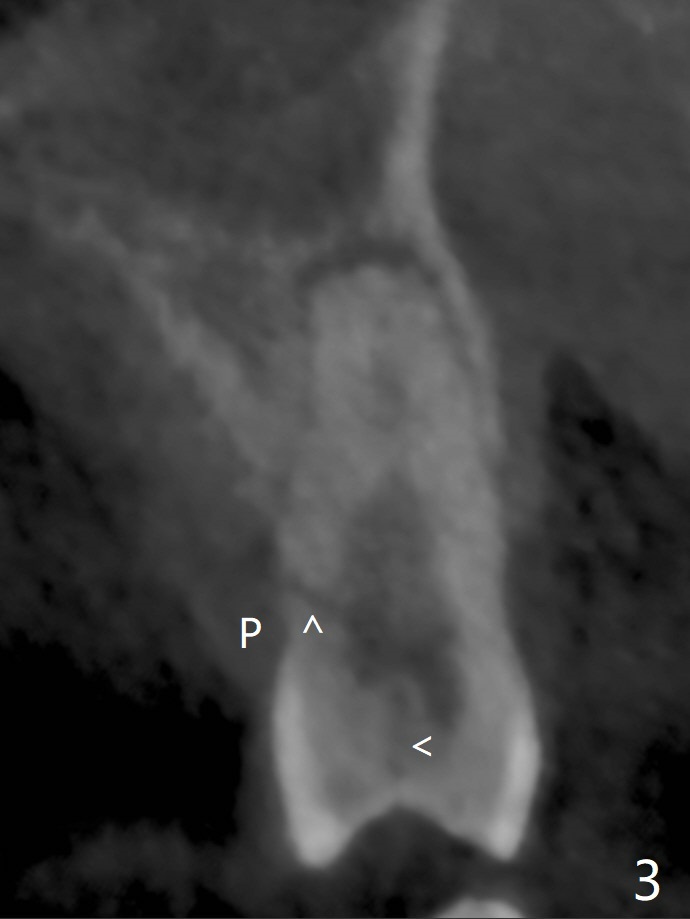

46岁男(每天两包烟,同意术前术后几天不吸烟)左上第一双尖牙折裂(图一,二(CT 3-D图)),由于折裂穿过牙髓(图三),摇动腭侧(P)断片特别痛。拔除患牙后(图四:黑色),由于窦底薄(图四:^),用锥形骨凿提升(图五(窦膜厚:黄虚线)),放置粘性骨粉后(图六),在牙槽窝腭侧骨壁中间开始钻洞(图七:红箭头),钻头尖一旦进入骨板,马上改变钻洞方向,与修复一致,然后穿过窦底(图八:绿箭头)由于窦膜已经提升,穿过窦底谅必安全。最后植入4x14或者17毫米软组织水平植体(图九),准备4毫米报废植体。Return to Protect Graft Clindamycin 前磨牙即种 Xin Wei, DDS, PhD, MS 1st edition 05/01/2021, last revision 05/03/2021